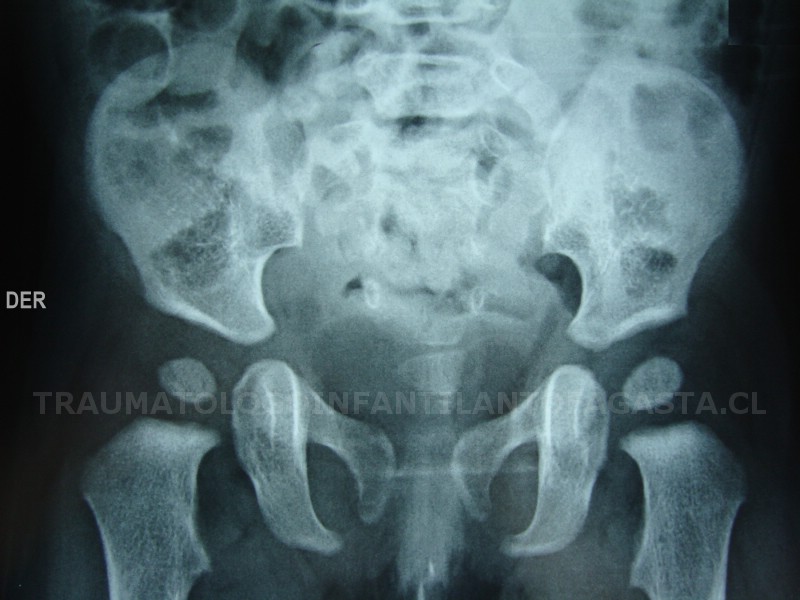

Displasia de caderas